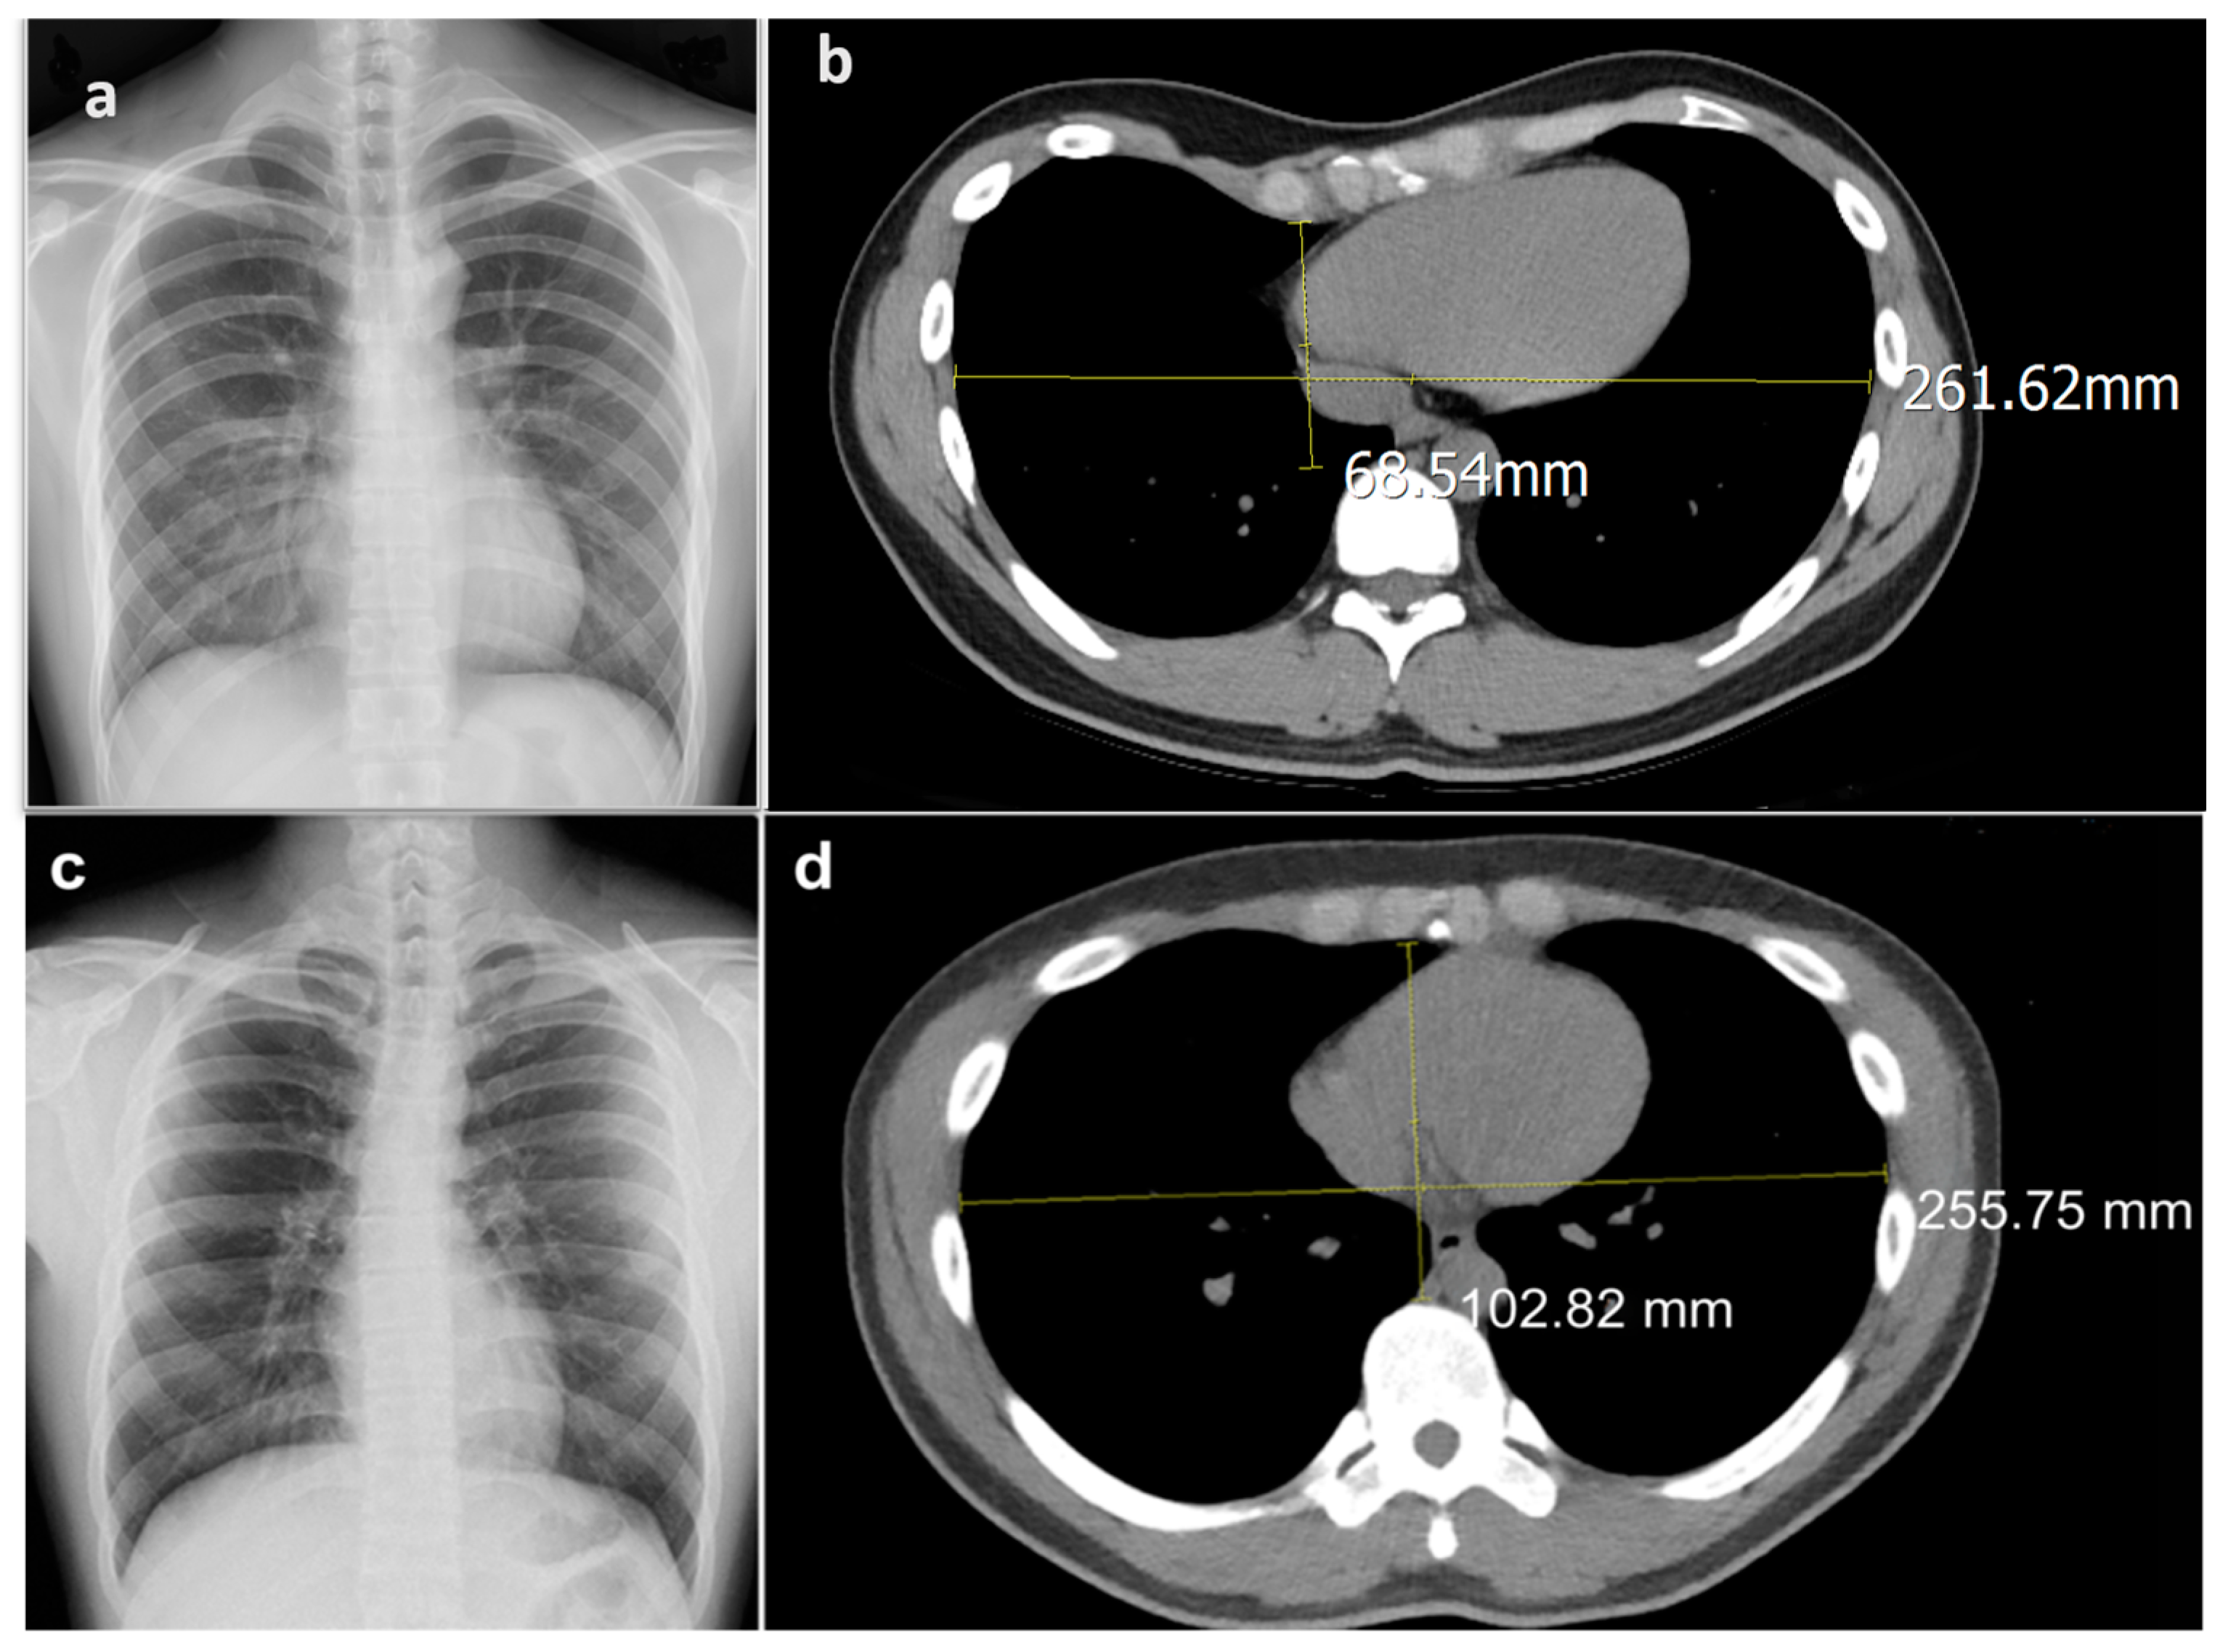

Figure 1.

Pectus excavatum is diagnosed by Haller index > 3.25. Calculation of Haller index by measurement of SVD (sternual-vertebral distance) divided by TD (transverse chest diameter) from chest computed tomography (CT). Sample images used in our study: (a) posteroanterior-view chest X-ray of a 24-year-old patient with PE with (b) CT calculated Haller index of 3.82. (c) Posteroanterior-view chest X-ray of a 24-year-old patient with no abnormal radiographic finding with (d) CT calculated Haller index of 2.49.

Of note is that the PE diagnosis is unlikely from frontal chest radiograph images without a chest lateral view or CT images.

Pectus excavatum can be corrected by a modified Nuss procedure, a minimally invasive method, where stainless-steel bridge metal bars are placed retrosternally to strut the depressed chest wall [4] Although surgical repair has been proven to improve cardiopulmonary function in patients with PE [5], there is much to be regretted considering some PE patients miss the opportunity for surgical correction at the optimal age due to a delayed diagnosis of the disease. Patients may feel embarrassed about their appearance and may not be willing to talk about it. Some patients may not even be aware of its existence, and therefore they cannot ascribe their exercise intolerance and cardiopulmonary symptoms to PE, making the accessibility of PE diagnosis more important. Clinically, the image diagnosis of PE still relies on manual measurement of the thoracic diameter on chest computed tomotraphy (CT). Physicians measure the maximum transverse diameter of the thoracic cage divided by the shortest distance from the sternal to the anterior vertebral body to get the Haller index, which can indicate the severity of pectus excavatum. The cut-off value of Haller index 3.25 has been widely used for pectus excavatum diagnosis for decades based on the preliminary report of Haller et al., which revealed that all patients who received operative repair had a Haller index greater than 3.25 (Figure 1) [6]. However, chest CTs are not economical and are not frequently requested imaging test compare to frontal view chest X-rays during routine health examination. Moreover, a chest CT examination takes 30~170 times more radiation dose exposure than a chest X-ray [7]. Since a human can hardly differentiate pectus excavatum from a frontal view chest X-ray, our proposal is to use artificial intelligence to accomplish this task. Our aim is to train a machine learning model to diagnose pectus excavatum from plain frontal chest radiography automatically, without the need for a chest CT. It would not only economize manual labor and medical expenses as a screening tool, but would also ensure that the potential diseased candidates could be screened out for surgical repair to improve their quality of life, while helping them to avoid extra radiation exposure.